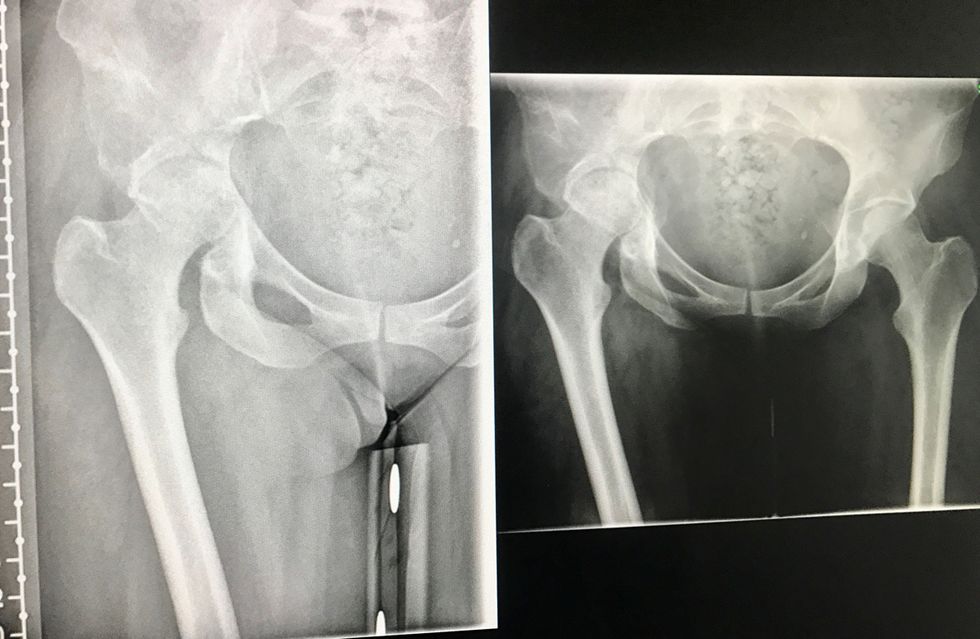

While Rachel Watkins, 40, was walking her four beloved dogs – Jack Russell, Maya, Springador, Ella, and rescue Greyhounds, Bruce and Vinnie – near her home in Okehampton, Devon, she shattered her right hip, which had already been in pain on and off for a year, leaving her in complete agony.

Somehow dragging herself back to the car, she phoned for help and was raced to Royal Devon and Exeter Hospital, where a scan revealed that a tumor had been silently growing in her hip joint, weakening it over time.

“Doctors told me that my hip joint was so fragile it was like an egg shell, and the fall had shattered it.

After ensuring her pets were safe, Rachel phoned for help and was taken straight to hospital, where an X Ray and CT scan were performed.

Not only had she broken her pelvis and shattered her hip, but a number of tumors had been discovered.

Further investigations concluded that she actually had stage four metastatic breast cancer, which had spread to her hip and ribs.